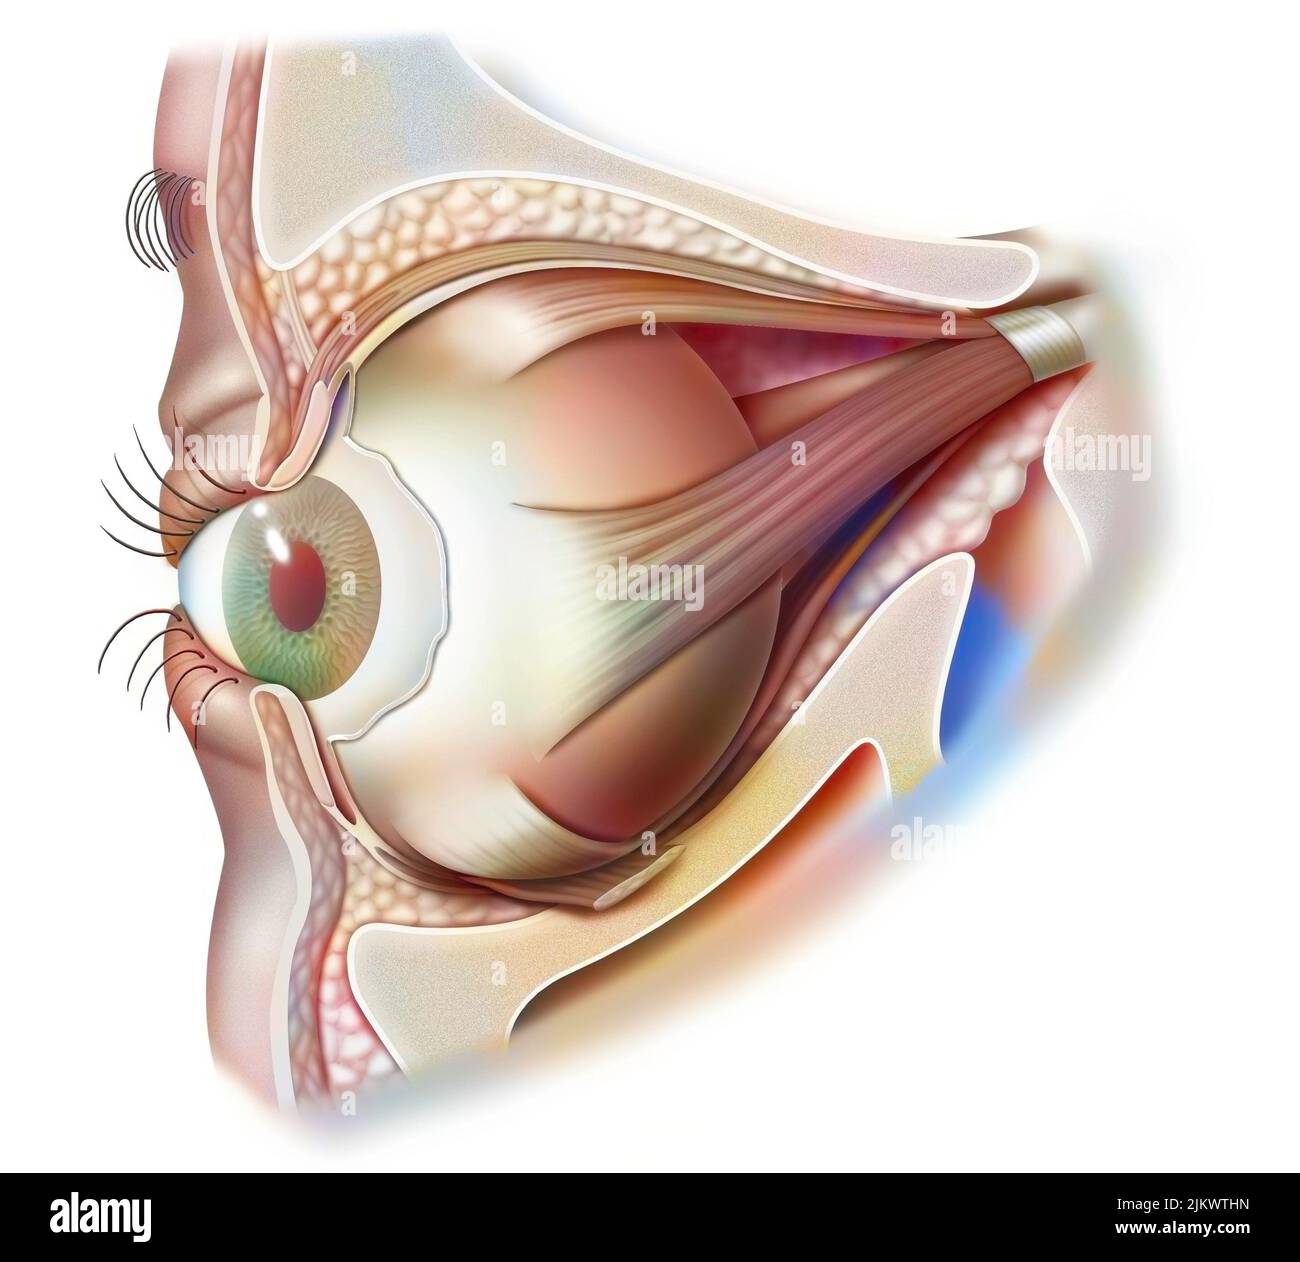

RF2JKWT9A–Oeil, cataracte, phacoémulsification - étape 2: Consiste à casser la lentille avec une sonde.